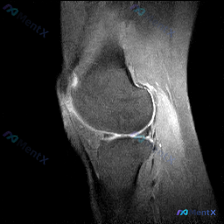

刚整理了一份很有启发的膝关节MRI读片病例,分享给大家,尤其能帮我们避避临床思维的坑。 病例核心影像信息 这是一例膝关节MRI T2序列矢状位影像,送检原因是怀疑存在半月板异常,系统评估各结构如下: 1. 骨骼关节软骨:股骨远端、胫骨近端、髌骨轮廓正常,股骨滑车和胫骨平台关节软骨大致平滑,无明显全层...

最近看到这份膝关节MRI读片请求,核心提示是软骨异常,整理了完整的资料和分析思路分享给大家: 基本影像信息 这份是膝关节矢状位MRI图像,属于T2加权/质子加权压脂序列,图像分辨率低、噪声大,仅能显示髌骨、股骨远端前部、胫骨近端前部和髌股关节局部区域,无法判断是内侧还是外侧层面。 影像具体发现 1....